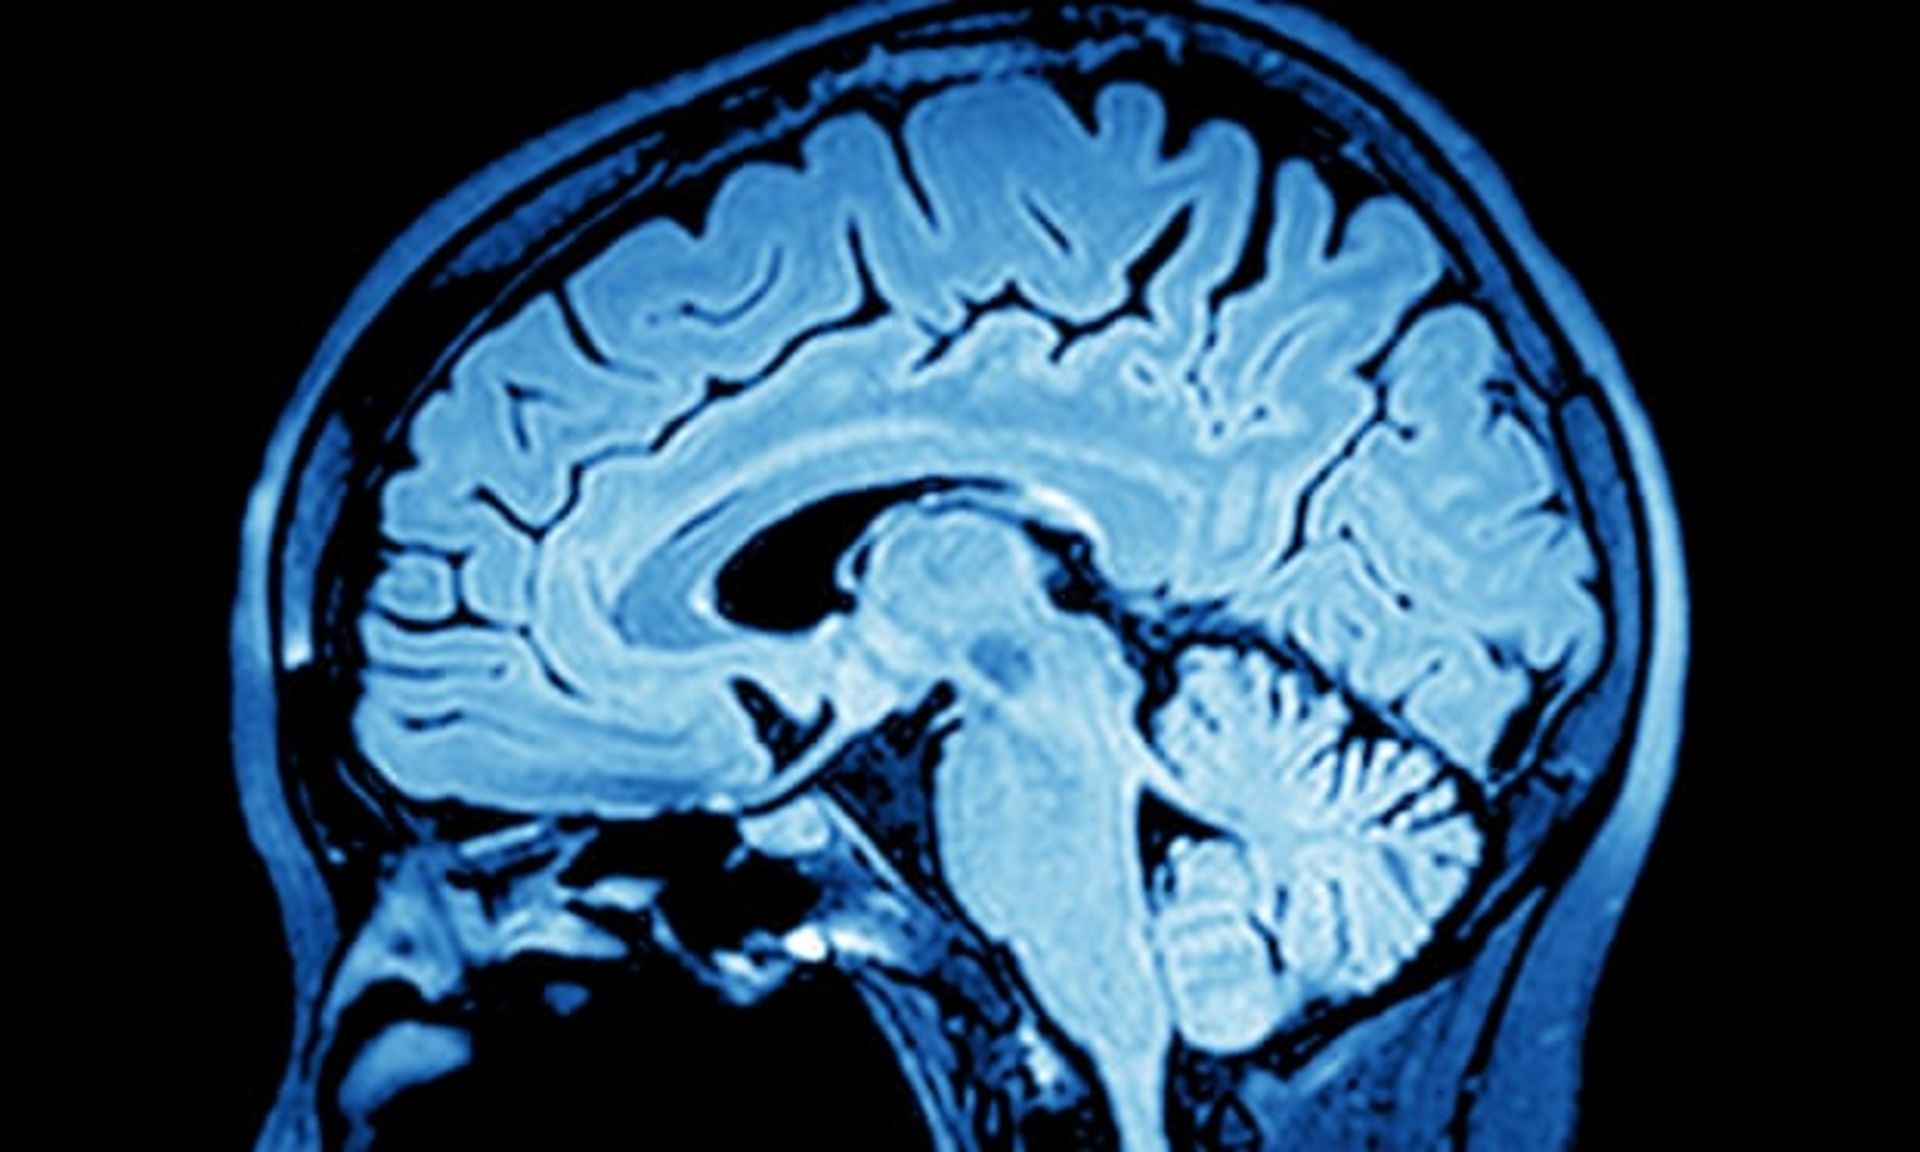

دکتر زیدرمن و همکارانش، آزمایشی را طراحی کردند تا ببینند مغز چگونه با افکار مربوط به مرگ دستوپنجه نرم میکند. محققان در این آزمایش سعی کردند تا با روشی سیگنالهایی از تعجب و حیرت در مغز ایجاد کنند و بهکمک این سیگنالها از وضعیت مغز در مقابله با افکار مرگ باخبر شوند. طی این آزمایش، از داوطلبان خواسته میشد که به چهرهی افرادی که در مانیتور ظاهر میشد نگاه کنند و از طرفی فعالیت مغز این داوطلبان در همین حین ارزیابی میشد.

گاهی صورت خود فرد یا گاهی صورت یک فرد غریبه روی صفحهی نمایش ظاهر میشد و سپس چهرهای متفاوت به داوطلبان نشان داده میشد. با دیدن تصویر آخرین چهره، مغز بهشدت متعجب میشد؛ زیرا این تصویر با آنچه مغز پیشبینی کرده بود مغایرت داشت. کلمات مختلفی بالای تصاویر نمایان میشد که در نیمی از موارد این کلمات مربوط به مرگ بودند، نظیر دفنکردن یا خاکسپاری.

نتیجهی جالبی که از آزمون به دست آمد این بود که دانشمندان متوجه شدند، زمانیکه کلمهی مربوط به مرگ روی عکس چهرهی خود فرد نمایش داده میشد، مغز داوطلب بلافاصله سیستم پیشبینی خود را غیرفعال میکرد یا کلمات را اصلا به خود نسبت نمیداد و دربارهی دیگران پیشبینی میکرد. بهعبارتی، مغز ارتباط میان خود فرد را با مرگ نمیپذیرفت و ارزیابیهای امواج مغز هیچگونه علامتی از تعجب و حیرت را ثبت نمیکردند.